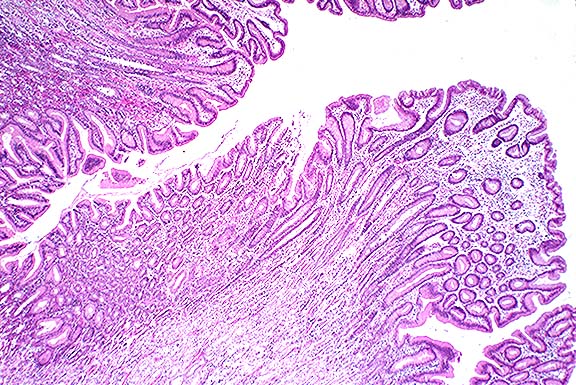

Case III - N93-184-8 (AFIP 2593935); one photo

Signalment: 8-year-old, female, baboon (Papio cynocephalus)

History: This animal had a history of weight loss and loose feces. It was euthanized.

Gross Pathology: The animal was emaciated. There was excessive clear fluid in the peritoneal and pericardial cavities. The small and large intestines were atonic and contained yellow fluid digesta. The glandular stomach was markedly irregularly thickened (approximately 10x normal; see gross photo.)

Laboratory Results: Low total protein; low sodium; culture of stomach and colon: unremarkable.

Contributor's Diagnosis and Comments: Hyperplastic foveolar gastropathy (Menetrier's disease); etiology undetermined.

Five baboon stomachs (out of 215 examined) with marked mucosal thickening and giant hypertrophic folds and nodules were found incidentally at necropsy. These baboons were thin and had chronic diarrhea. The condition was not diagnosed clinically. The increased mucosal thickening was due to hyperplasia of the foveolar epithelium. Two of the stomachs were classified as Menetrier's disease (MD) and three as varioliform lymphocytic gastritis (VLG). These cases were histologically identical with those gastropathies in humans and may represent a useful model of disease in the future. According to Wolfsen et al, and Cheli, human hypertrophic gastropathies should be classified into a) MD - mucosal hyperplasia with little or no inflammation, b) VLG - multiple nodular hyperplasia with or without intraepithelial lymphocytosis and as c) HLG - diffuse hypertrophic lymphocytic gastritis.

This case was classified as MD because of the diffusely increased mucosal thickness due primarily to foveolar hyperplasia. The section also has numerous glandular cysts, limited inflammation and a normal number of intraepithelial lymphocytes (<16/100 epithelial cells).

Case 5-3. Stomach. Note mucosal hyperplasia with giant folds. 2X

AFIP Diagnosis: Stomach: Hyperplasia, mucosal, diffuse, marked, with mild lymphoplasmacytic and eosinophilic gastritis, baboon (Papio cynocephalus), primate.

Conference Note: The Division of Gastrointestinal Pathology of the AFIP also reviewed this case and agreed that the giant folds are consistent with Menetrier's disease (MD).

In humans, MD is a gastric giant folds disease syndrome, but all parts of the syndrome may not be present at the same time. The full syndrome includes giant folds, gastric protein loss, and decreased gastric acid production, accompanied by a histologic complex that includes foveolar hyperplasia and distortion, glandular atrophy, and edema but little inflammation, in the lamina propria.5 The gastric pits (foveolae) are unusually elongated, and frequently extend from the surface to the base of the mucosa. They occasionally penetrate the muscularis mucosa, ending as cysts surrounded by smooth muscle. The superficial lamina propria is usually edematous, and may contain low numbers of plasma cells and eosinophils.

The cause of MD is unknown; however, it is now being linked to excessive levels of growth factors, particularly transforming growth factor alpha (TGFa). A histologically and clinically identical condition has been produced in transgenic mice that overexpressed TGFa in their stomachs.5